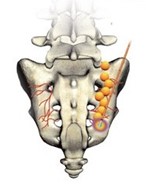

Sacro-iliac joints are synovial joints formed between the Ilium and the Sacrum and are important components of pelvic girdle. They are present on both sides and connect the hip bones postero-laterally. The main function of this joint is to bear the weight of the axial skeleton and transfer it equally to the hip bones which is finally distributed to the femurs bilaterally.

In cases of severely degenerated Sacro-iliac joints, only joint injections are not helpful. In these cases, Lateral branches of Sacral nerves which specifically supply the SI joints are targeted with the help of radiofrequency ablator, which bring about Wallerian degeneration in these nerves, thus blocking the pain signals and bringing about pain relief.